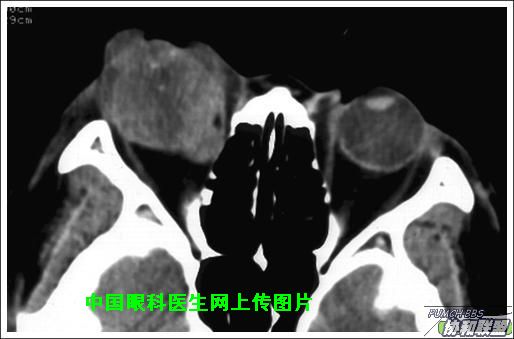

出院后半年发现右眼出现肿物,增长较快,随来京再次就诊(图1),转来我科。门诊检查发现:右眼无光感,结膜下肿物,突出睑裂。眼球突出,上移位。眶外侧可触及硬性肿物。超声(图2),CT(图3),MRI(图456)显示如图.